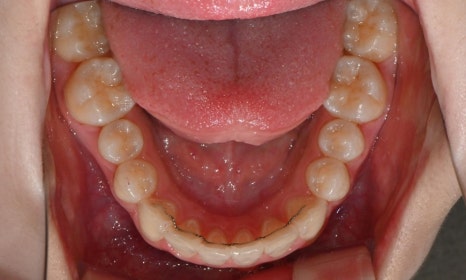

2025.3. 초진 (앞니 경미한 총생과 과개교합) - 연세정원치과

정밀진단 결과 위아래 앞니가 약간 겹쳐 있어 배열이 고르지 않은 상태였으며, 약간의 과개교합이 동반된 상태였습니다. 다만 골격적인 문제나 안모 불균형은 없었고, 측면에서도 돌출감 없이 비교적 안정적인 안모를 유지하고 있었습니다.

이번 케이스는 인비절라인 Comprehensive로 치료를 진행하였으며, 치아 이동은 과도하지 않게 단계적으로 진행하기 위해 치간삭제를 최소한으로 적용하며 공간을 확보하는 방향으로, 총 33단계의 장치를 통해 치아 이동을 계획하였습니다.